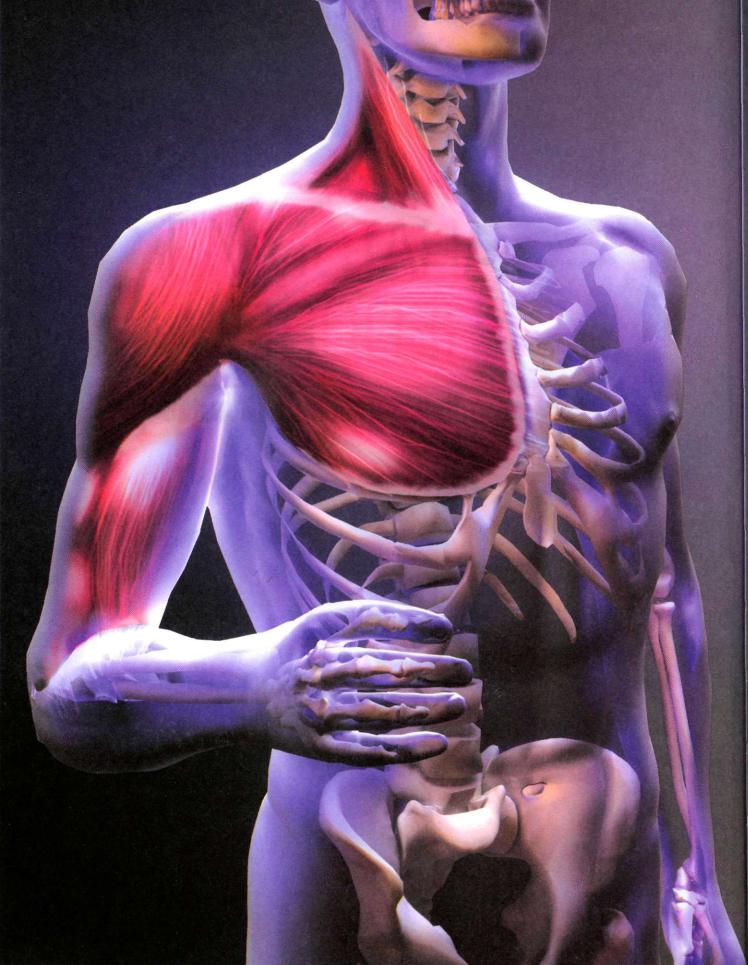

Изображения и визуализация внутренних органов человека